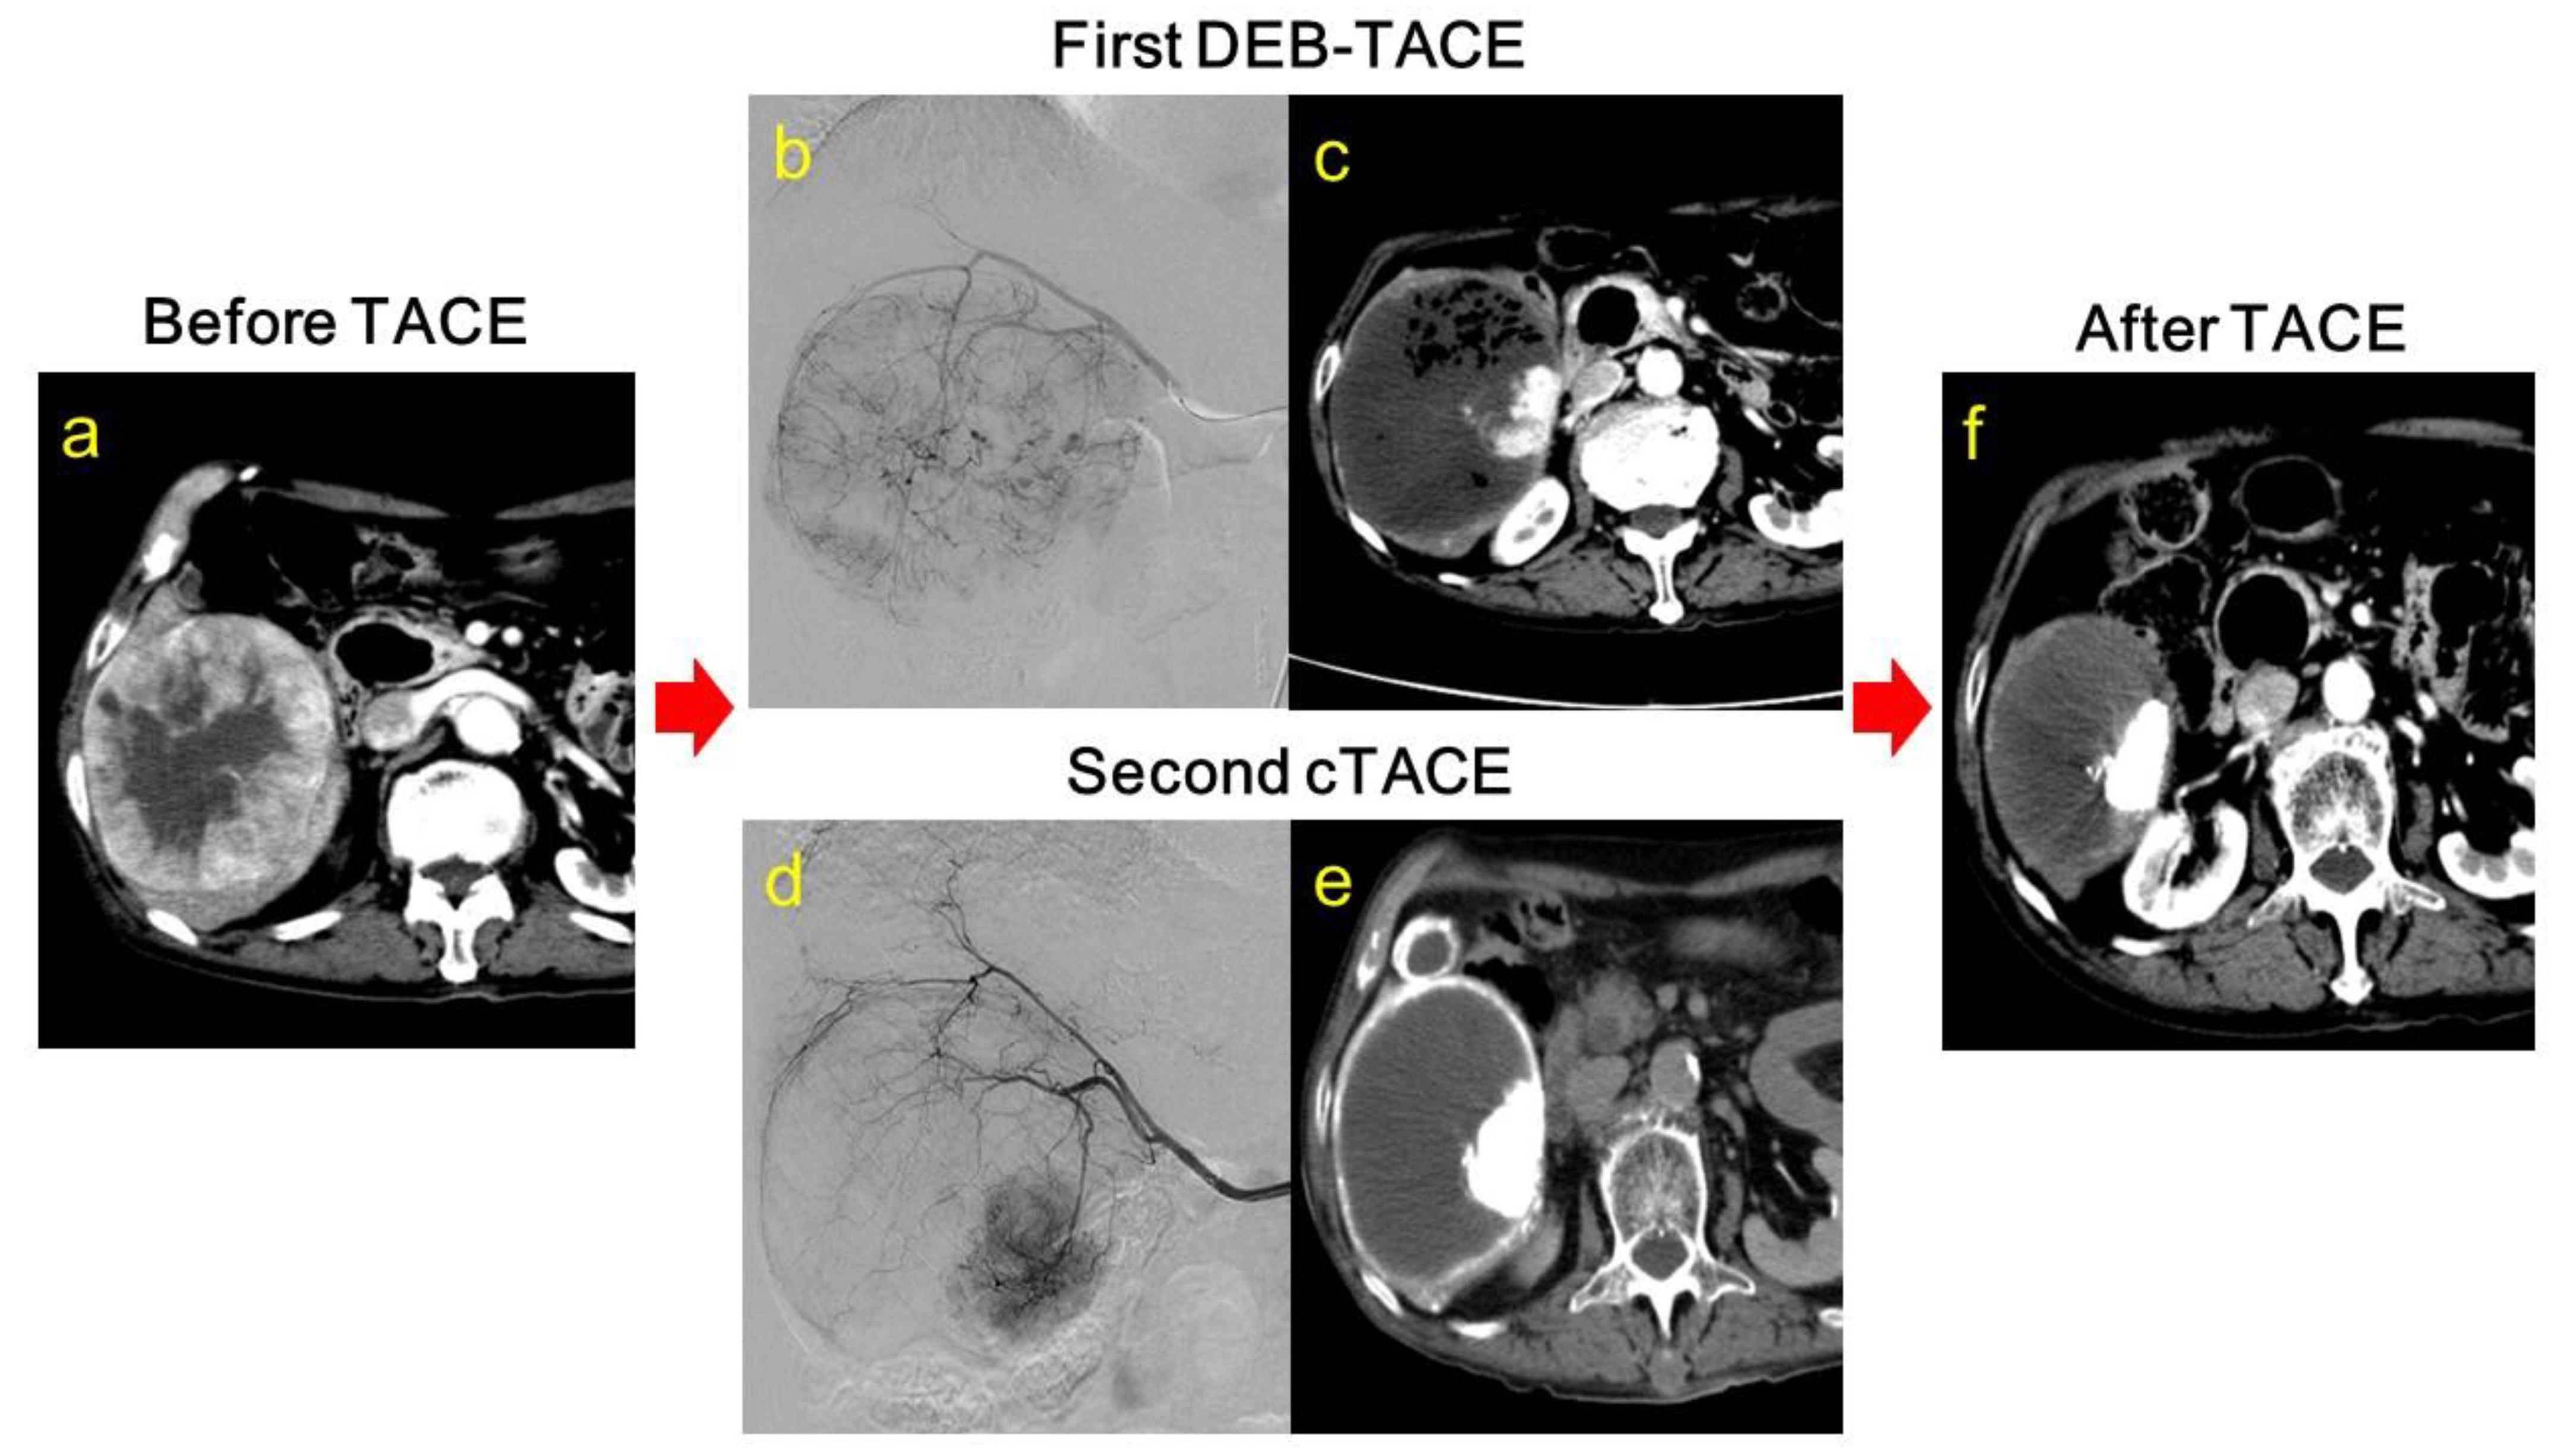

2.2. DEB-TACE Procedures

2.3. cTACE Procedures and Timing of Additional cTACE